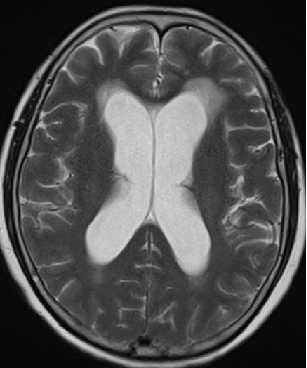

2013-8-2 CT

腰穿脑压240